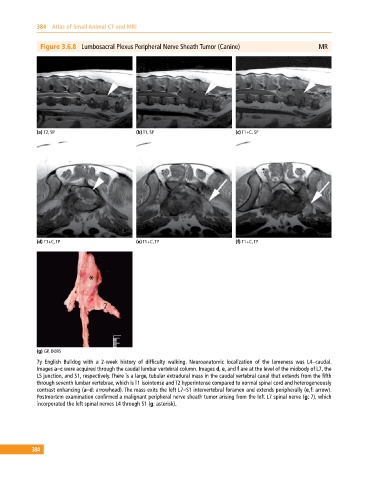

Figure 3.6.8 Lumbosacral Plexus Peripheral Nerve Sheath Tumor (Canine) MR

(a) T2, SP (b) T1, SP (c) T1+C, SP

(d) T1+C, TP (e) T1+C, TP (f) T1+C, TP

(g) GP, DORS

7y English Bulldog with a 2‐week history of difficulty walking. Neuroanatomic localization of the lameness was L4–caudal.

Images a–c were acquired through the caudal lumbar vertebral column. Images d, e, and f are at the level of the midbody of L7, the

LS junction, and S1, respectively. There is a large, tubular extradural mass in the caudal vertebral canal that extends from the fifth

through seventh lumbar vertebrae, which is T1 isointense and T2 hyperintense compared to normal spinal cord and heterogeneously

contrast enhancing (a–d: arrowhead). The mass exits the left L7–S1 intervertebral foramen and extends peripherally (e,f: arrow).

Postmortem examination confirmed a malignant peripheral nerve sheath tumor arising from the left L7 spinal nerve (g: 7), which

incorporated the left spinal nerves L4 through S1 (g: asterisk).